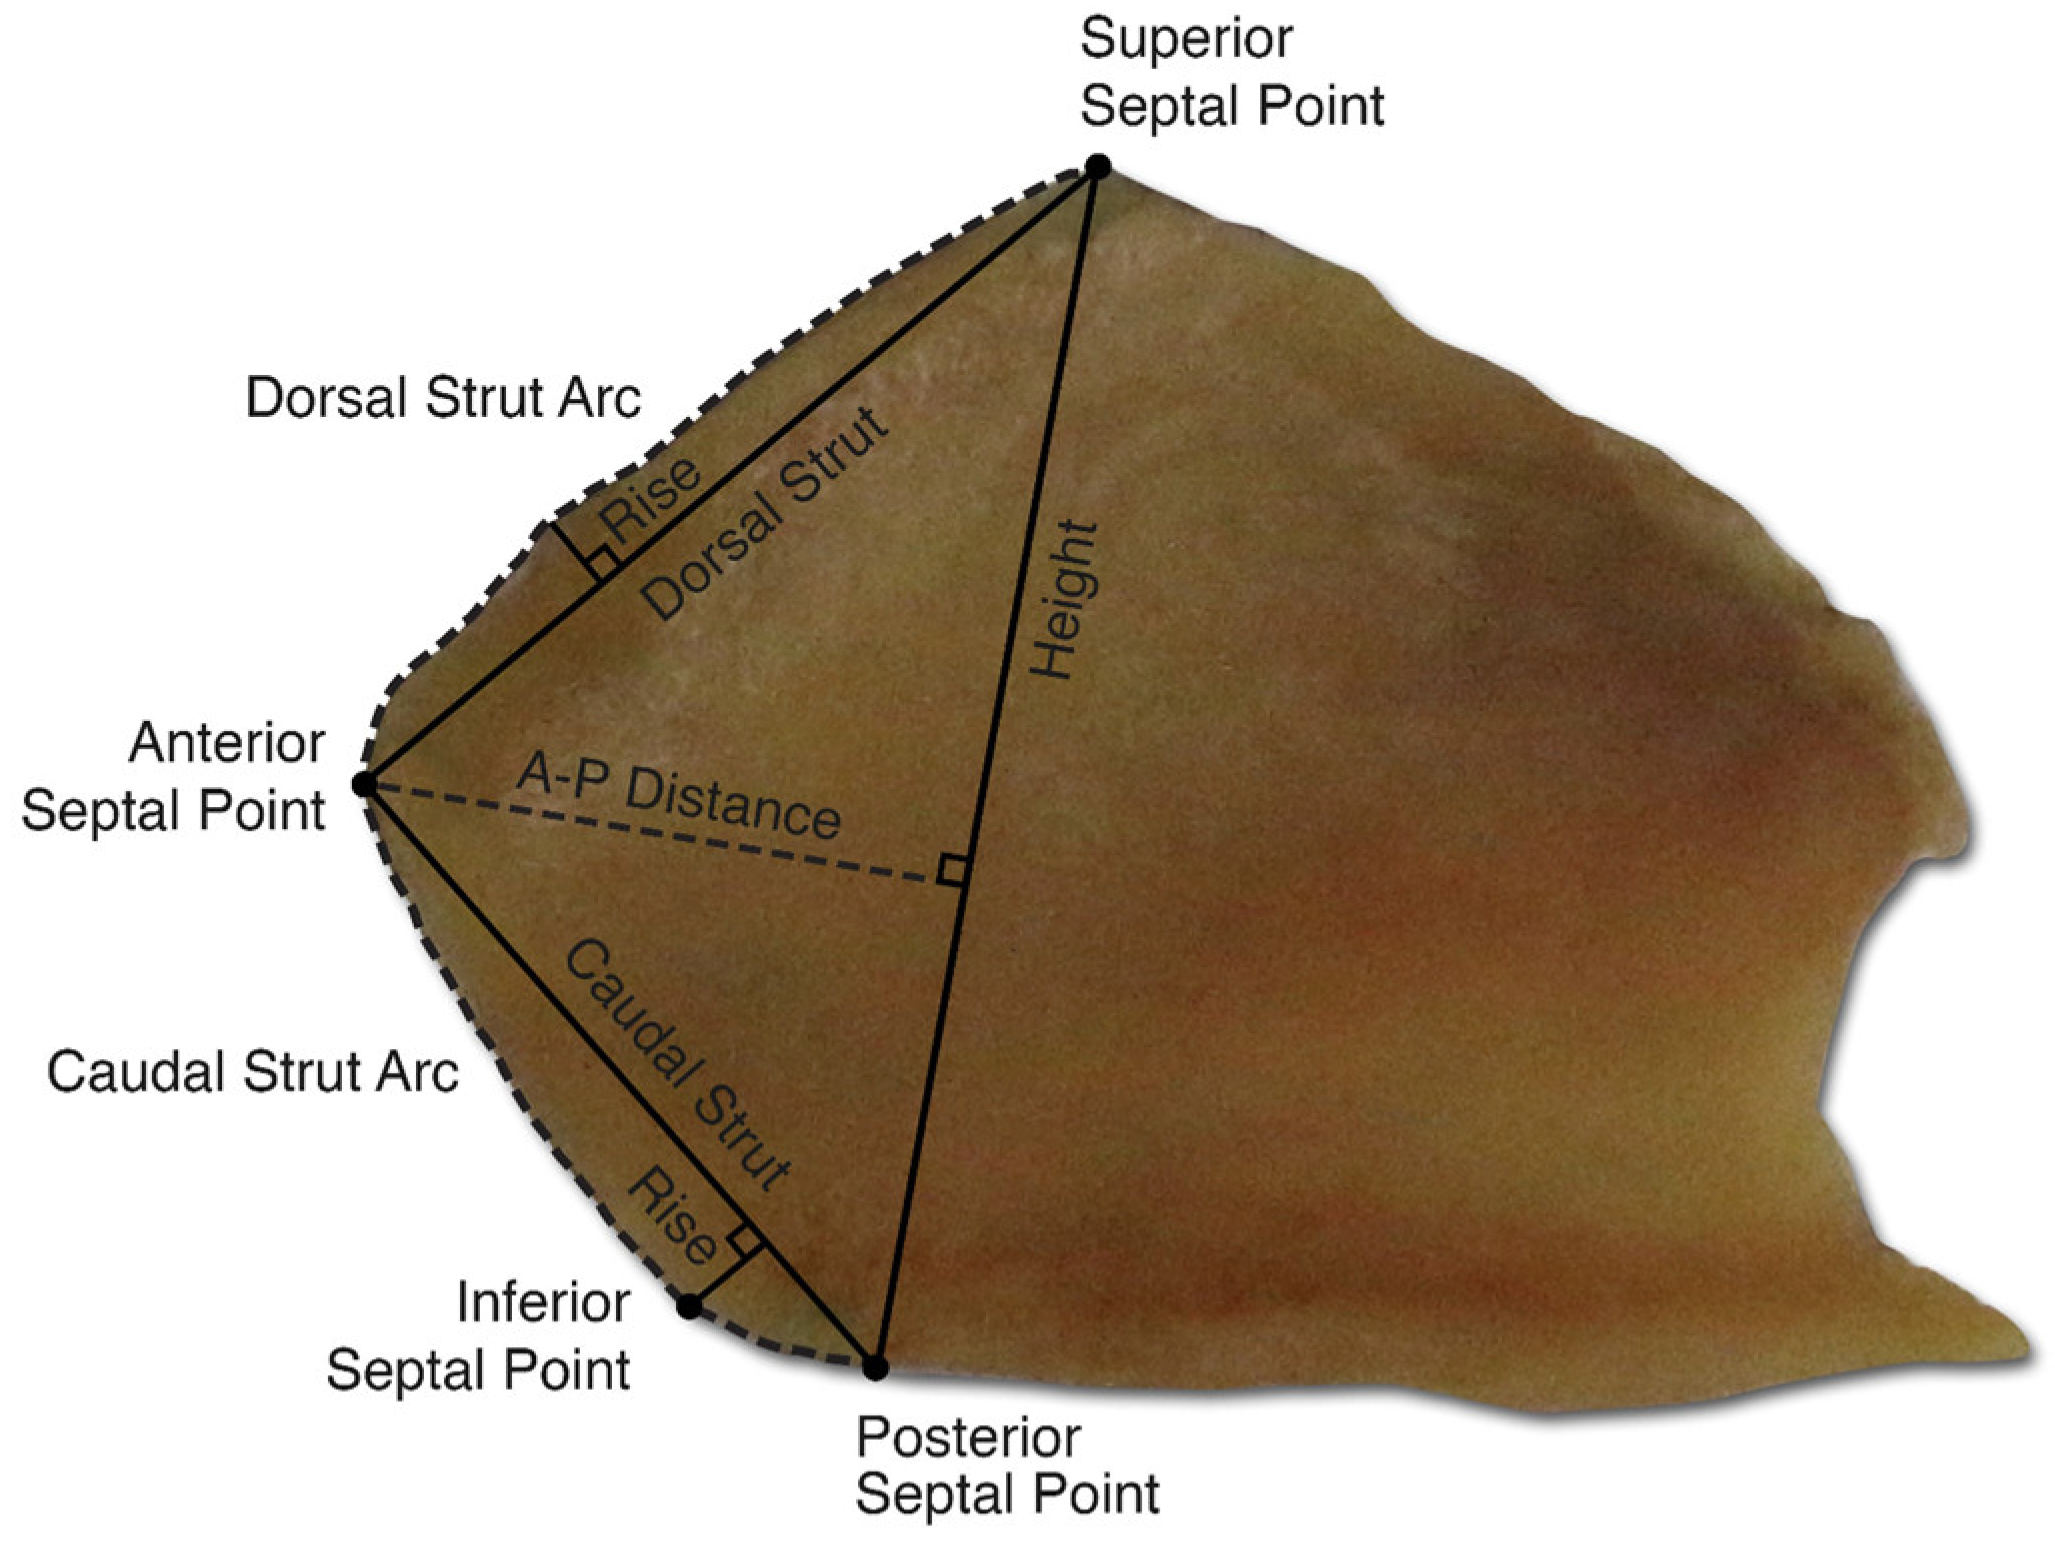

- Lavernia, L.; Brown, W.E.; Wong, B.J.F.; Hu, J.C.; Athanasiou, K.A. Toward tissue-engineering of nasal cartilages. Acta Biomater. 2019, 88, 42–56. [Google Scholar] [CrossRef] [PubMed]

- Popko, M.; Bleys, R.L.A.W.; De Groot, J.-W.; Huizing, E.H. Histological structure of the nasal cartilages and their perichondrial envelope. I. The septal and lobular cartilage. Rhinology 2007, 45, 148–152. [Google Scholar] [PubMed]